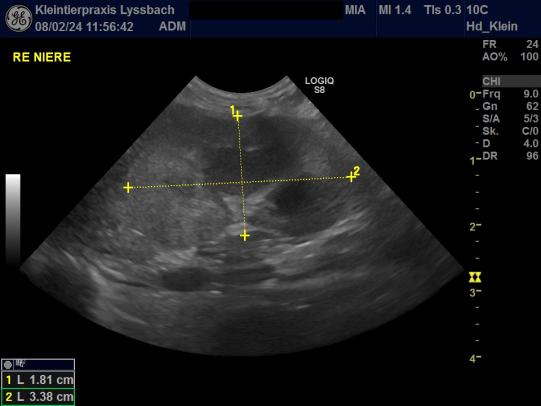

Zur genaueren Abklärung wird nun ein Bauchultraschall durchgeführt. Die Nieren erscheinen in Grösse und Form recht unauffällig, sie sind im Ultraschall aber etwas echogener ("heller") als üblich und der Übergang von Rinde zu Mark ist etwas verwischt. Diese Befunde sind nicht beweisend für ein Nierenproblem, weshalb wir eine weitere Urinprobe gekühlt und per Kurier in ein externes Labor zur weiteren Untersuchung einschicken.